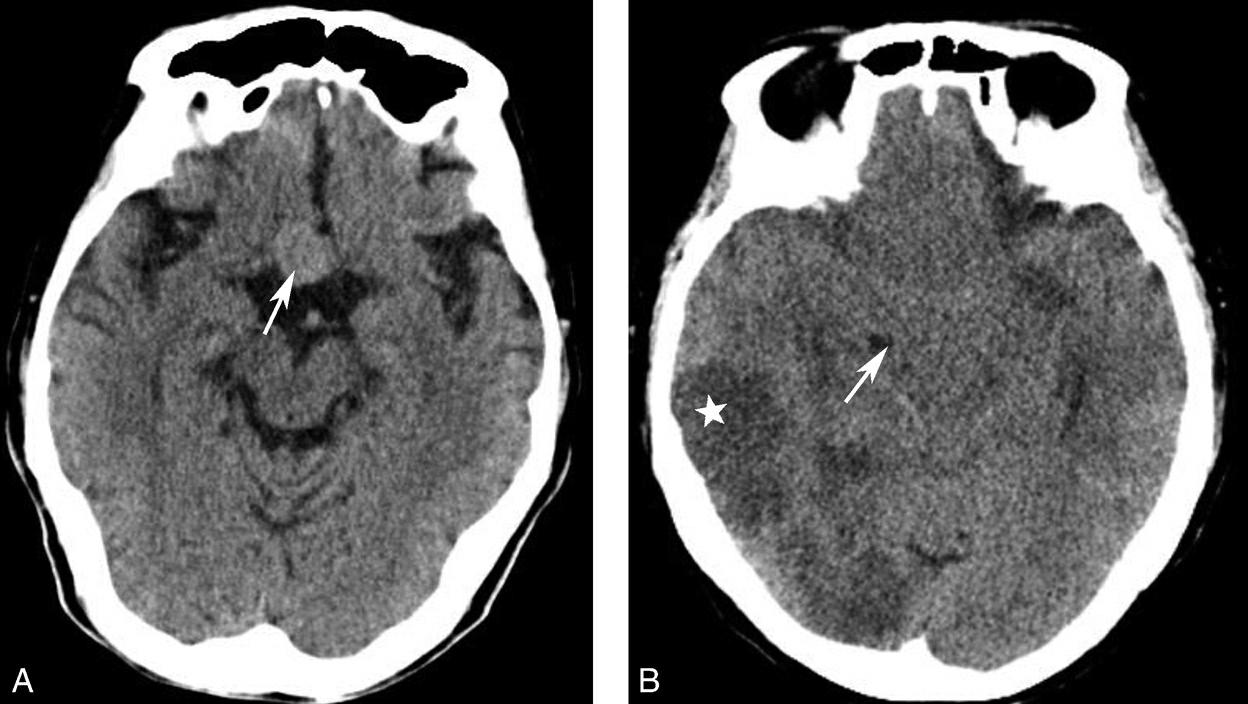

鞍上池是该层面需要重点观察的部位。其形态及密度的改变均提示病变(图1-2-18、图1-2-19),例如鞍上池失去正常五角星或六角星形态、甚至闭塞,或者鞍上池密度升高或不均匀。此外,环池闭塞多见于颅内压严重增高的患者,为诊断脑疝的影像学依据(图1-2-20)。

图1-2-18 鞍上池形态改变

A.鞍上池前角消失,失去正常六角星形态;此例为垂体腺瘤向鞍上生长,占据此区域所致(箭);B.鞍上池闭塞;此病例为双侧大脑半球多发大面积梗死(☆),弥漫性脑肿胀,导致鞍上池闭塞(箭)

图1-2-20 环池闭塞

右侧颞叶脑内大血肿(★),产生严重的占位效应,环池受压闭塞(箭),脑疝形成